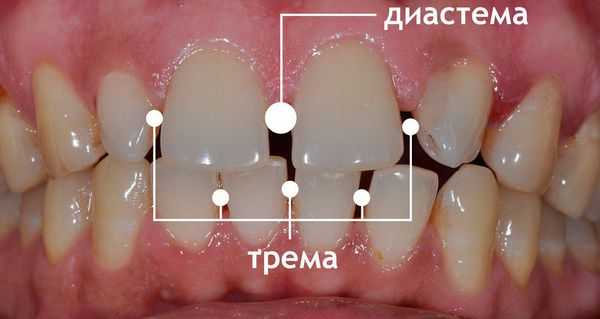

Диастема – видимый межзубный промежуток, разделяющий центральные резцы верхнего (реже – нижнего) зубного ряда. Диастема не только представляет собой эстетический недостаток, но также способствует нарушению речи, возникновению коммуникативных и психологических трудностей. Уточнение причин и сопутствующих диастеме аномалий проводится с помощью стоматологического осмотра, внутриротовой рентгенографии, ортопантомографии, изучения диагностических моделей челюстей. Лечение диастемы может осуществляться терапевтическими (эстетическая реставрация), ортопедическими (коронки, виниры), хирургическими (пластика уздечки верхней губы или языка), ортодонтическими (вестибулярные пластинки, брекеты) методами.

Тремы – промежутки между зубами. Основные жалобы сводятся к наличию эстетического дефекта. Диагностика трем включает анализ данных анамнеза, клинический осмотр, рентгенографию, ТРГ, антропометрические измерения моделей. Для периода старения временного прикуса характерны физиологические тремы, не требующие ортодонтического вмешательства. Лечение трем у пациентов с постоянным прикусом направлено на восстановление целостностности зубных рядов, достижение тесного контакта между боковыми поверхностями зубов. Если тремы являются одним из симптомов прогнатии или прогении, показана ортодонтическая коррекция прикуса.

Тремы – отсутствие тесного контакта между зубами. По своей сути тремы вторичны, то есть являются следствием другого физиологического или патологического процесса. Считают, что промежутки между зубами передаются генетически, как и неправильный прикус. Если у одного из родителей отсутствует плотный контакт между зубами и это обусловлено не вторичной адентией, то вероятность проявления патологии у детей составляет 50%. Тремы одинаково часто диагностируют у представителей обоих полов. Патология может становиться причиной постоянного травмирования десен с развитием воспалительных осложнений. Из-за длительной задержки кусочков пищи в межзубных промежутках возрастает вероятность кариеса. Основные методы устранения промежутков между зубами – протезирование или ортодонтическая коррекция.

Определение болезни. Причины заболевания

Диастема (щербинка) — это непропорционально большой промежуток между двумя рядом стоящими зубами. Такое эстетическое нарушение часто доставляет человеку психологический дискомфорт [1] .

Расстояние между зубами при диастеме составляет от 2 до 6 мм, но иногда может достигать 1 см. Чаще всего промежутки появляются между передними резцами верхней челюсти. На нижней челюсти диастемы встречаются крайне редко [2] .

Диастема — увеличенный межзубный промежуток в зоне улыбки. Чаще всего это — щель в 1-6 мм между центральными резцами верхней челюсти. «Щербинка» может появиться и на нижней челюсти. При любом расположении она привлекает внимание, портит эстетику улыбки, может ухудшать состояние всей зубочелюстной системы.